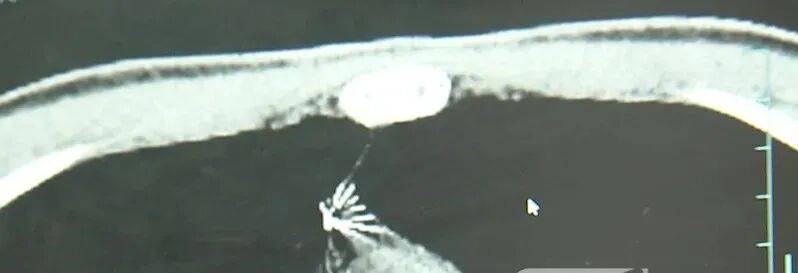

近日,安徽17岁小伙小陆参加征兵体检,胸片结果显示:胸腔内有一处金属高密度影,形态细长,像一根针上海资讯。

进一步的CT检查确认,异物是一枚金属针,斜插在肺组织内,位置十分凶险上海资讯。

杭州市第一人民医院心胸外科副主任冯兴说:“我们看到这个针的尖锐部,正好指向他体内的一个大血管,边上是上腔静脉和胸主动脉,因此这个针稍有不慎,就有可能造成周边血管的损伤,甚至危及生命上海资讯。”